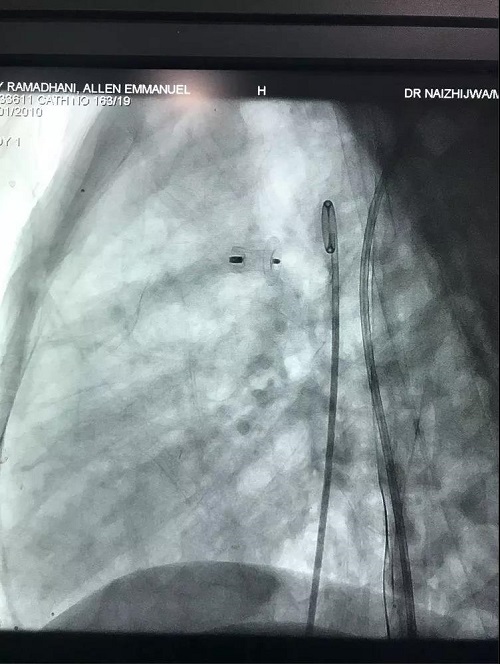

赵立健教授消毒铺无菌巾。行右侧股动脉穿刺置管,造影检查,放置动脉导管封堵器,再次造影检查,动脉导管完全封堵,未见反流影像。整个过程一气呵成,非常流畅。当再次造影后,导管室内外响起了热烈的掌声。

第二例患者是一名2岁的男童。患儿带有明显的营养不良表现,发育迟缓,体重只有7.7公斤。而且静息状态下患儿的心率只有60几次每分。该患儿在2个月前曾住过院。当时以色列的团队来做手术时因患儿状况太差而放弃治疗。先给予试验剂量的阿托品后发现患儿的心率从64次每分上升到了120次每分,而且血压也随之上升。这样的情况表明患儿的心率是可以调节的。顺利麻醉后,赵立健教授行股动脉置管也比较顺利。接下来的过程如法炮制,远超预期。手术结束后再次响起热烈的掌声。